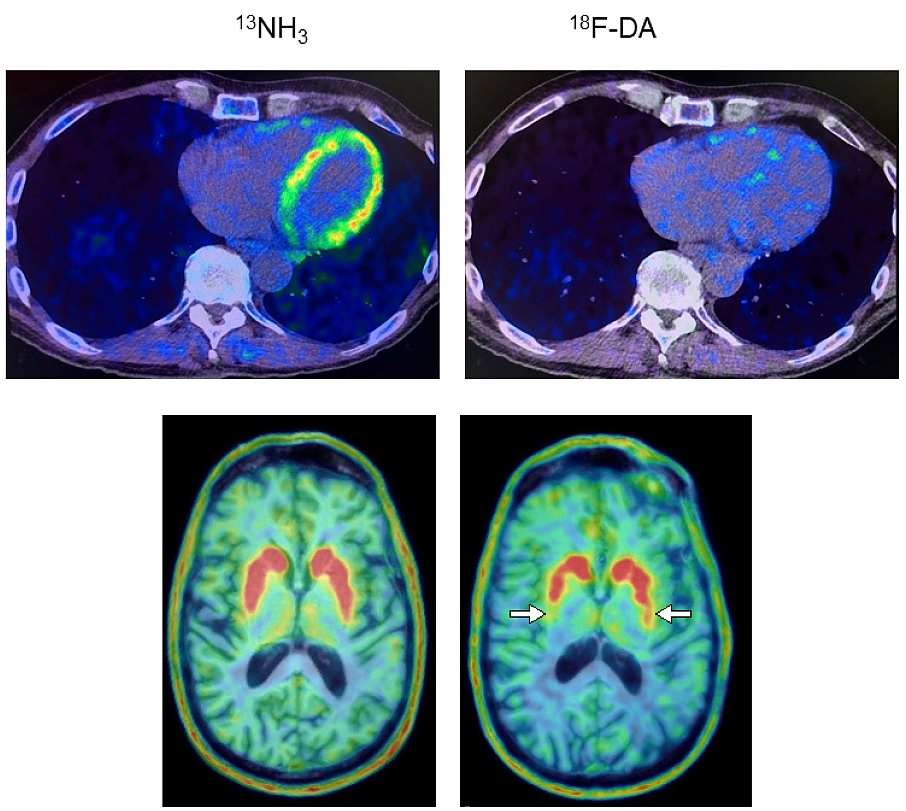

They also noted that promising radiotracers such as F-18 APN-1607 and F-18 PI-2620 have been developed to provide even more specific detail on atypical parkinsonism subtypes, and with further study could greatly aid in early diagnosis.